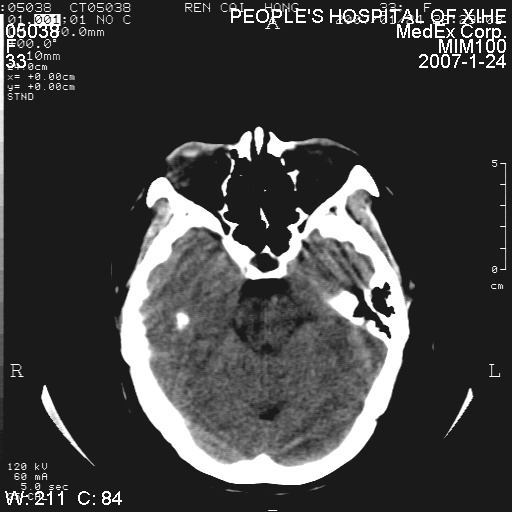

以下是引用卜一在2007-1-25 6:40:00的发言:[br]左侧额叶囊实混杂性病灶,多考虑胶质细胞瘤(ⅱ-ⅲ级),建议增强检查。[br]支持!

以下是引用wwwwtyy在2007-1-25 0:27:00的发言:[br]胶质瘤可能性大,不除外脑白质病变,建议强化

以下是引用守望可可西里在2007-1-25 0:13:00的发言:[br]左侧额叶囊实混杂性病灶,多考虑胶质细胞瘤(ⅱ-ⅲ级),建议增强检查!